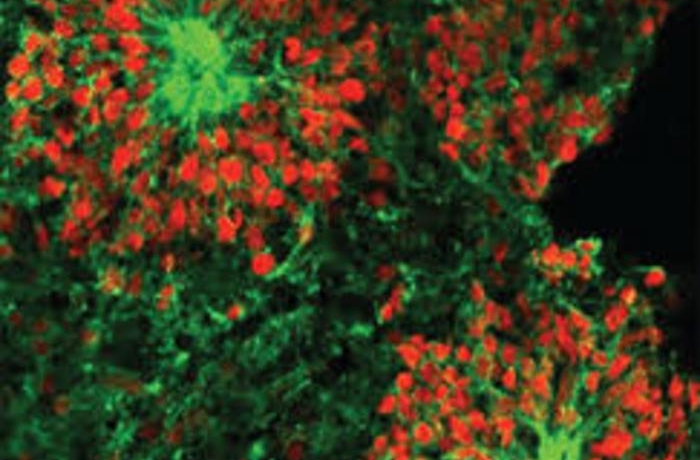

Международная группа исследователей отправила крошечные модели мозга на Международную космическую станцию (МКС)...